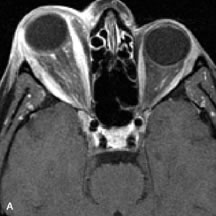

Inflammatory and Lymphoproliferative Lesions

Inflammatory conditions of the orbit, both idiopathic (inflammatory pseudotumor) and those of known causes, have been found to be hypointense to fat and isointense to muscle on Tl-weighted studies and isointense or slightly hyperintense to fat on T2-weighted images (Fig. 21).50,64,69 The more fibrous or sclerosing varieties have less signal intensity on T2-weighted images. Marked enhancement is seen in pseudotumor infiltrates after gadolinium administration.70 The same signal characteristics are demonstrated in patients with Tolosa-Hunt syndrome, with mass lesions seen in the cavernous sinuses and orbital apices.71

Fig. 21. A. T1-weighted MR scan demonstrates diffuse enlargement of both the superior rectus and levator palpebrae superioris muscles (single arrows). The involvement of the tendinous insertions and preseptal soft tissues (open arrows) as well as lack of involvement of other muscles helps differentiate this entity from thyroid-associated orbitopathy. B and C. Postcontrast fat-suppressed T1-weighted MR scans demonstrate extensive enhancement of the involved muscles as well as the preseptal (open arrows) and perinuscular tissues (double arrows).